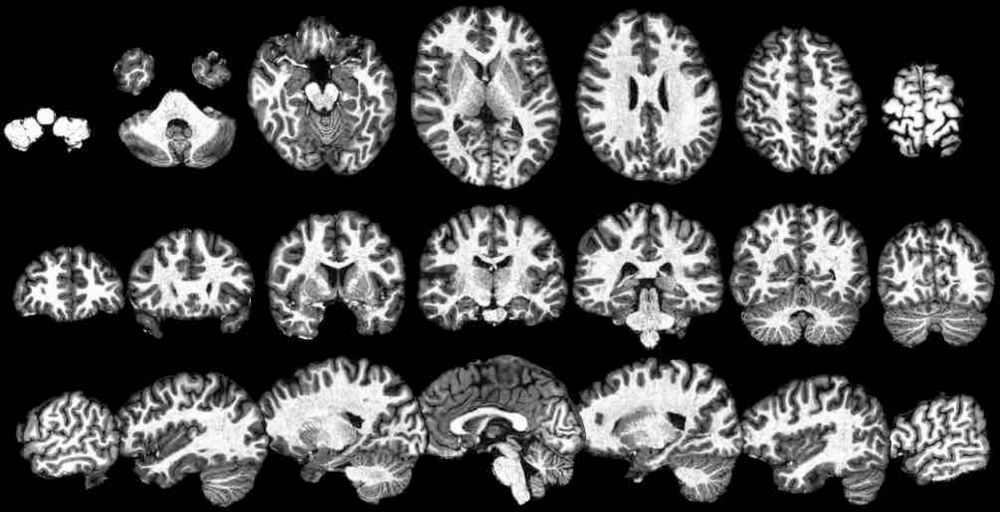

The question we ask: when do face responses arise in human infant cortex?

Graphic showing two alternative theories of the sequence and timing of development of cortical face responses: slow and sequential, or early and parallel.